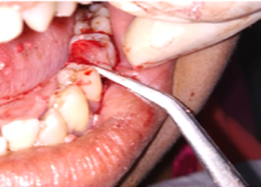

Hemisectomy

Post-OP Clinical View